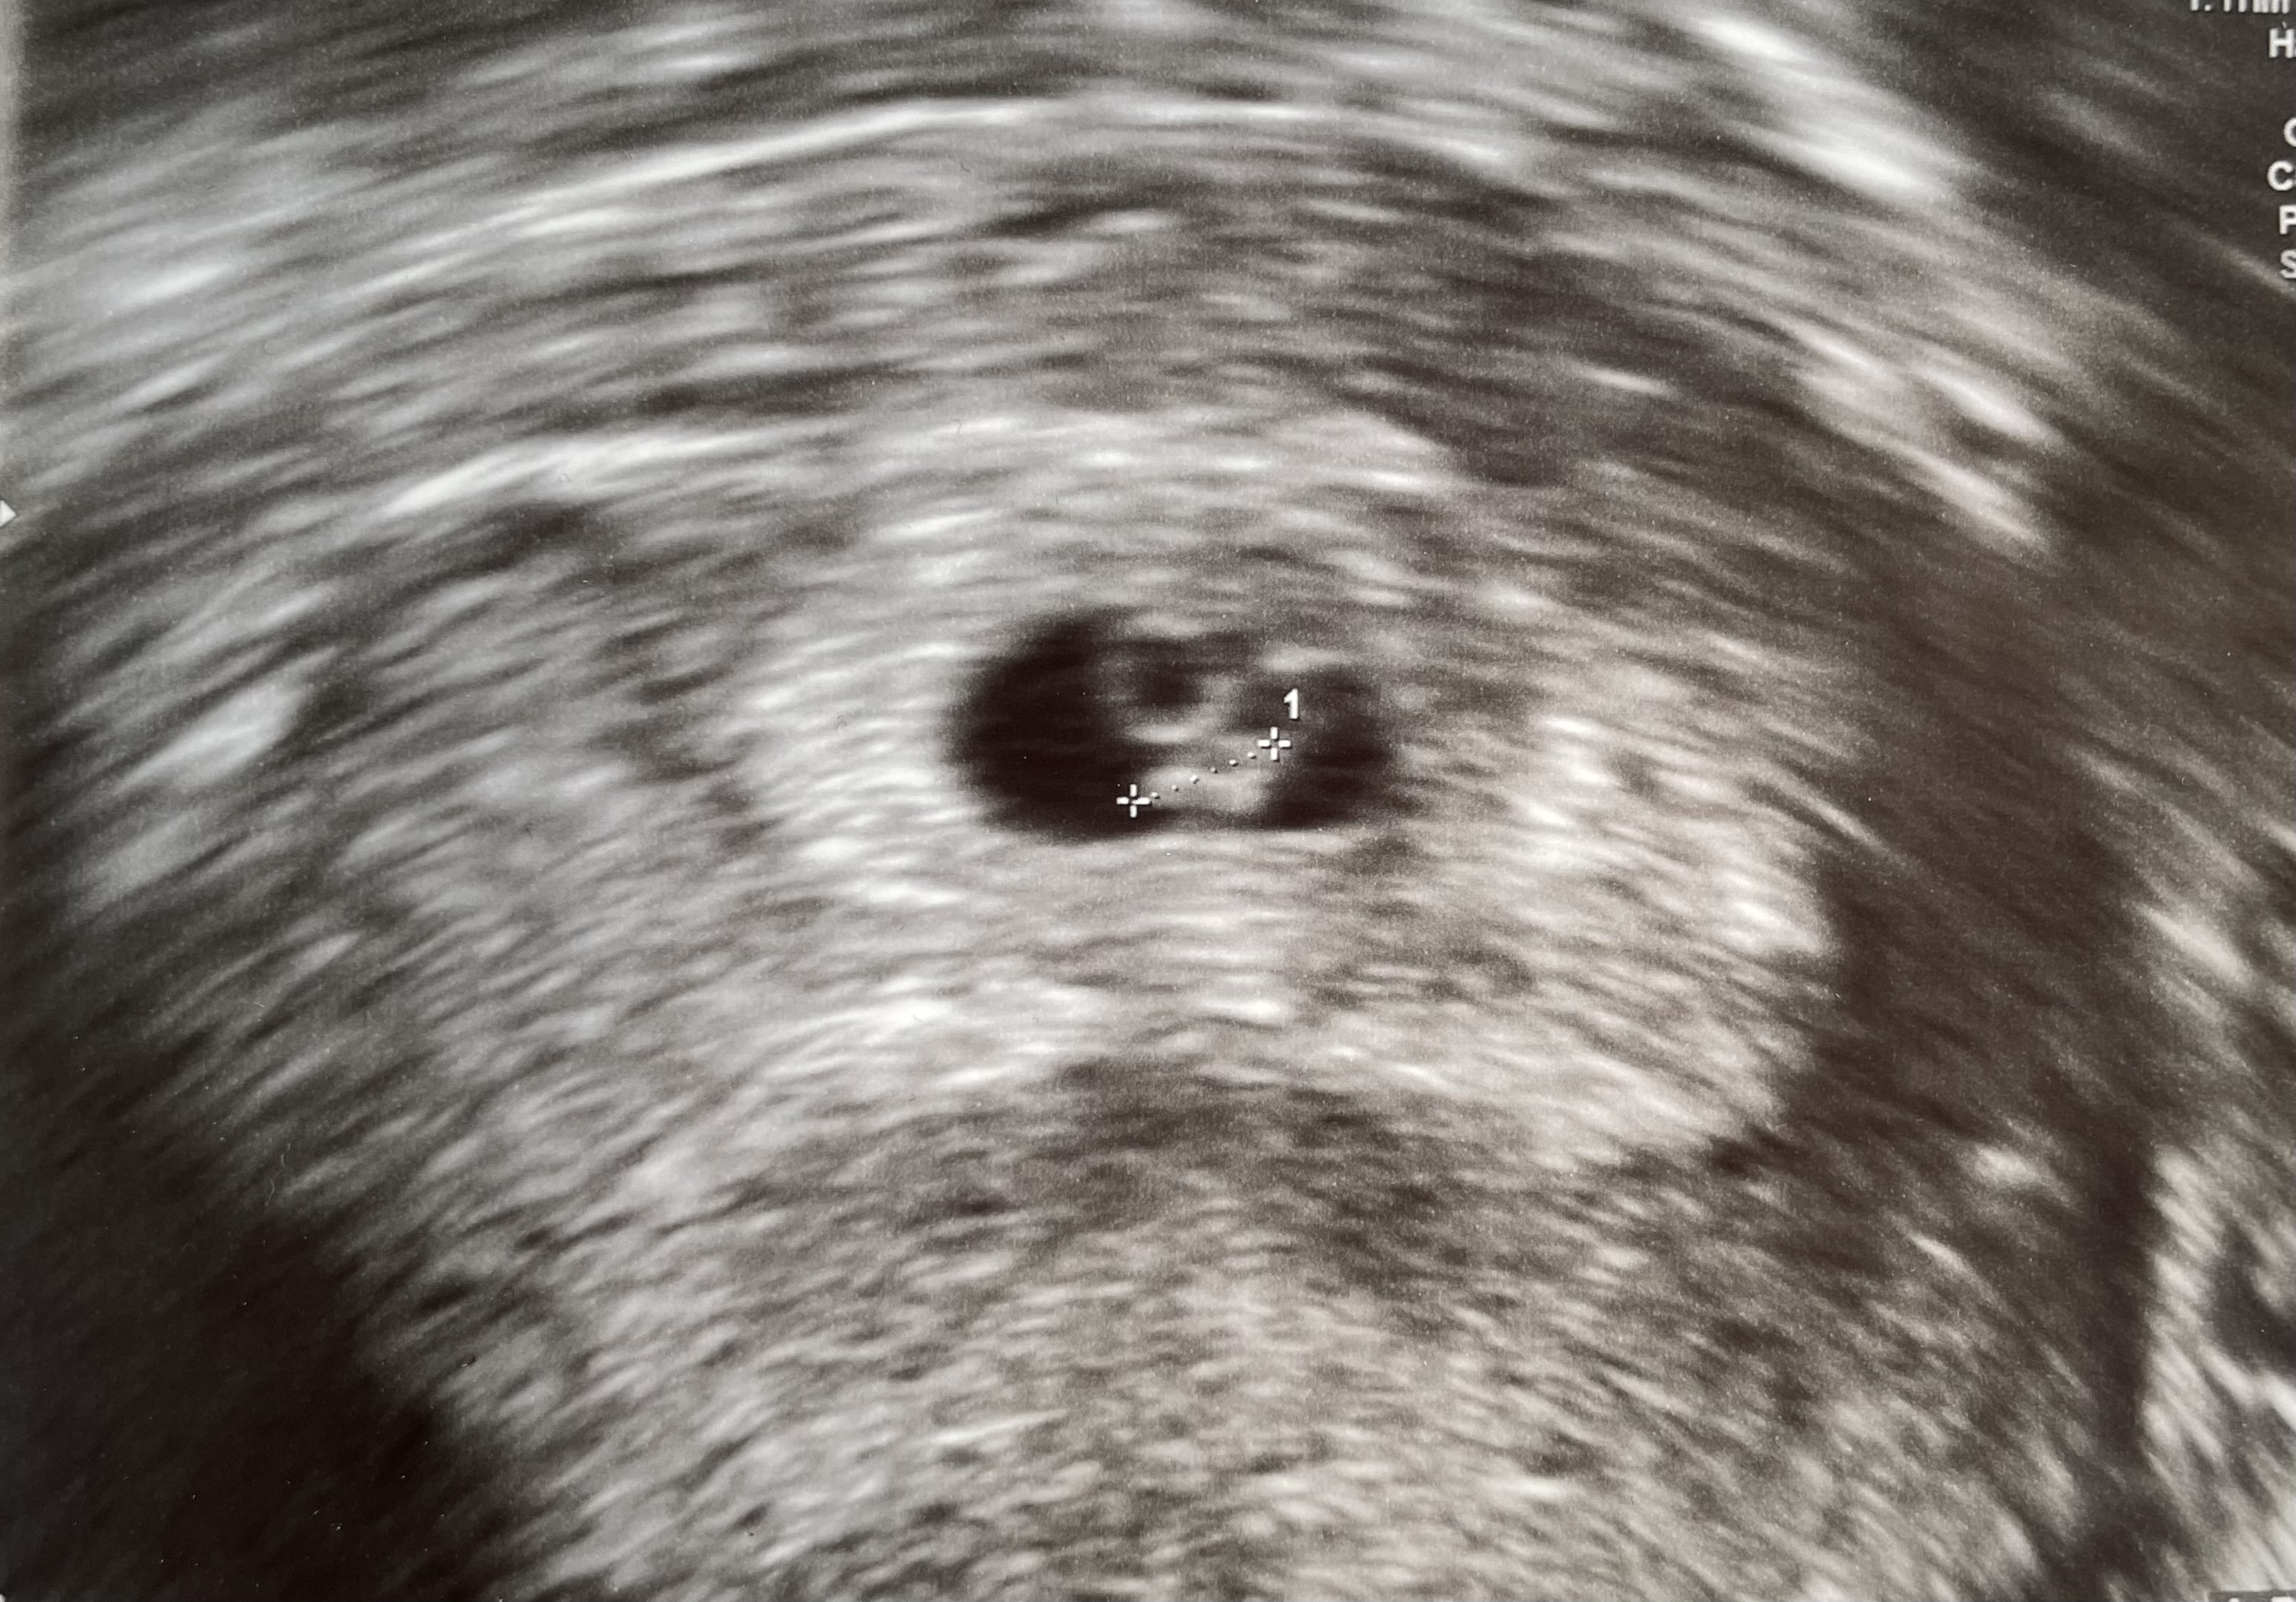

Åå se der da, fine lille frøet7+2!

Fine lille frøet! Jeg tror dette er et av de fineste bildene jeg noen gang har sett <3

Skikkelig nervøs før timen idag, jeg var sikker på at gyn ikke kom til å finne noe, en tom fostersekk eller et dødt frø... Jeg holdt nesten pusten mens hun lette - så først et svart "hull" som jeg må vet er noe fylt ned væske, og tenkte at det må være livmor med fostervann! Jeg passet på å ikke drikke noe før timen, slik at et ikke kunne forveksles med blæren.

Inni var en liten klump, og jeg fikk klump i magen når hun lette, og plutselig ba meg holde pusten. Så - endelig, så jeg noe som blinket fort på skjermen, og jeg forsto at det måtte være hjertet! Tre sekund etter bekreftet hun det, og både jeg og mannen pustet lettet ut. Jeg tror vi begge har vært mye mer nervøse enn vi har gitt uttrykk for!